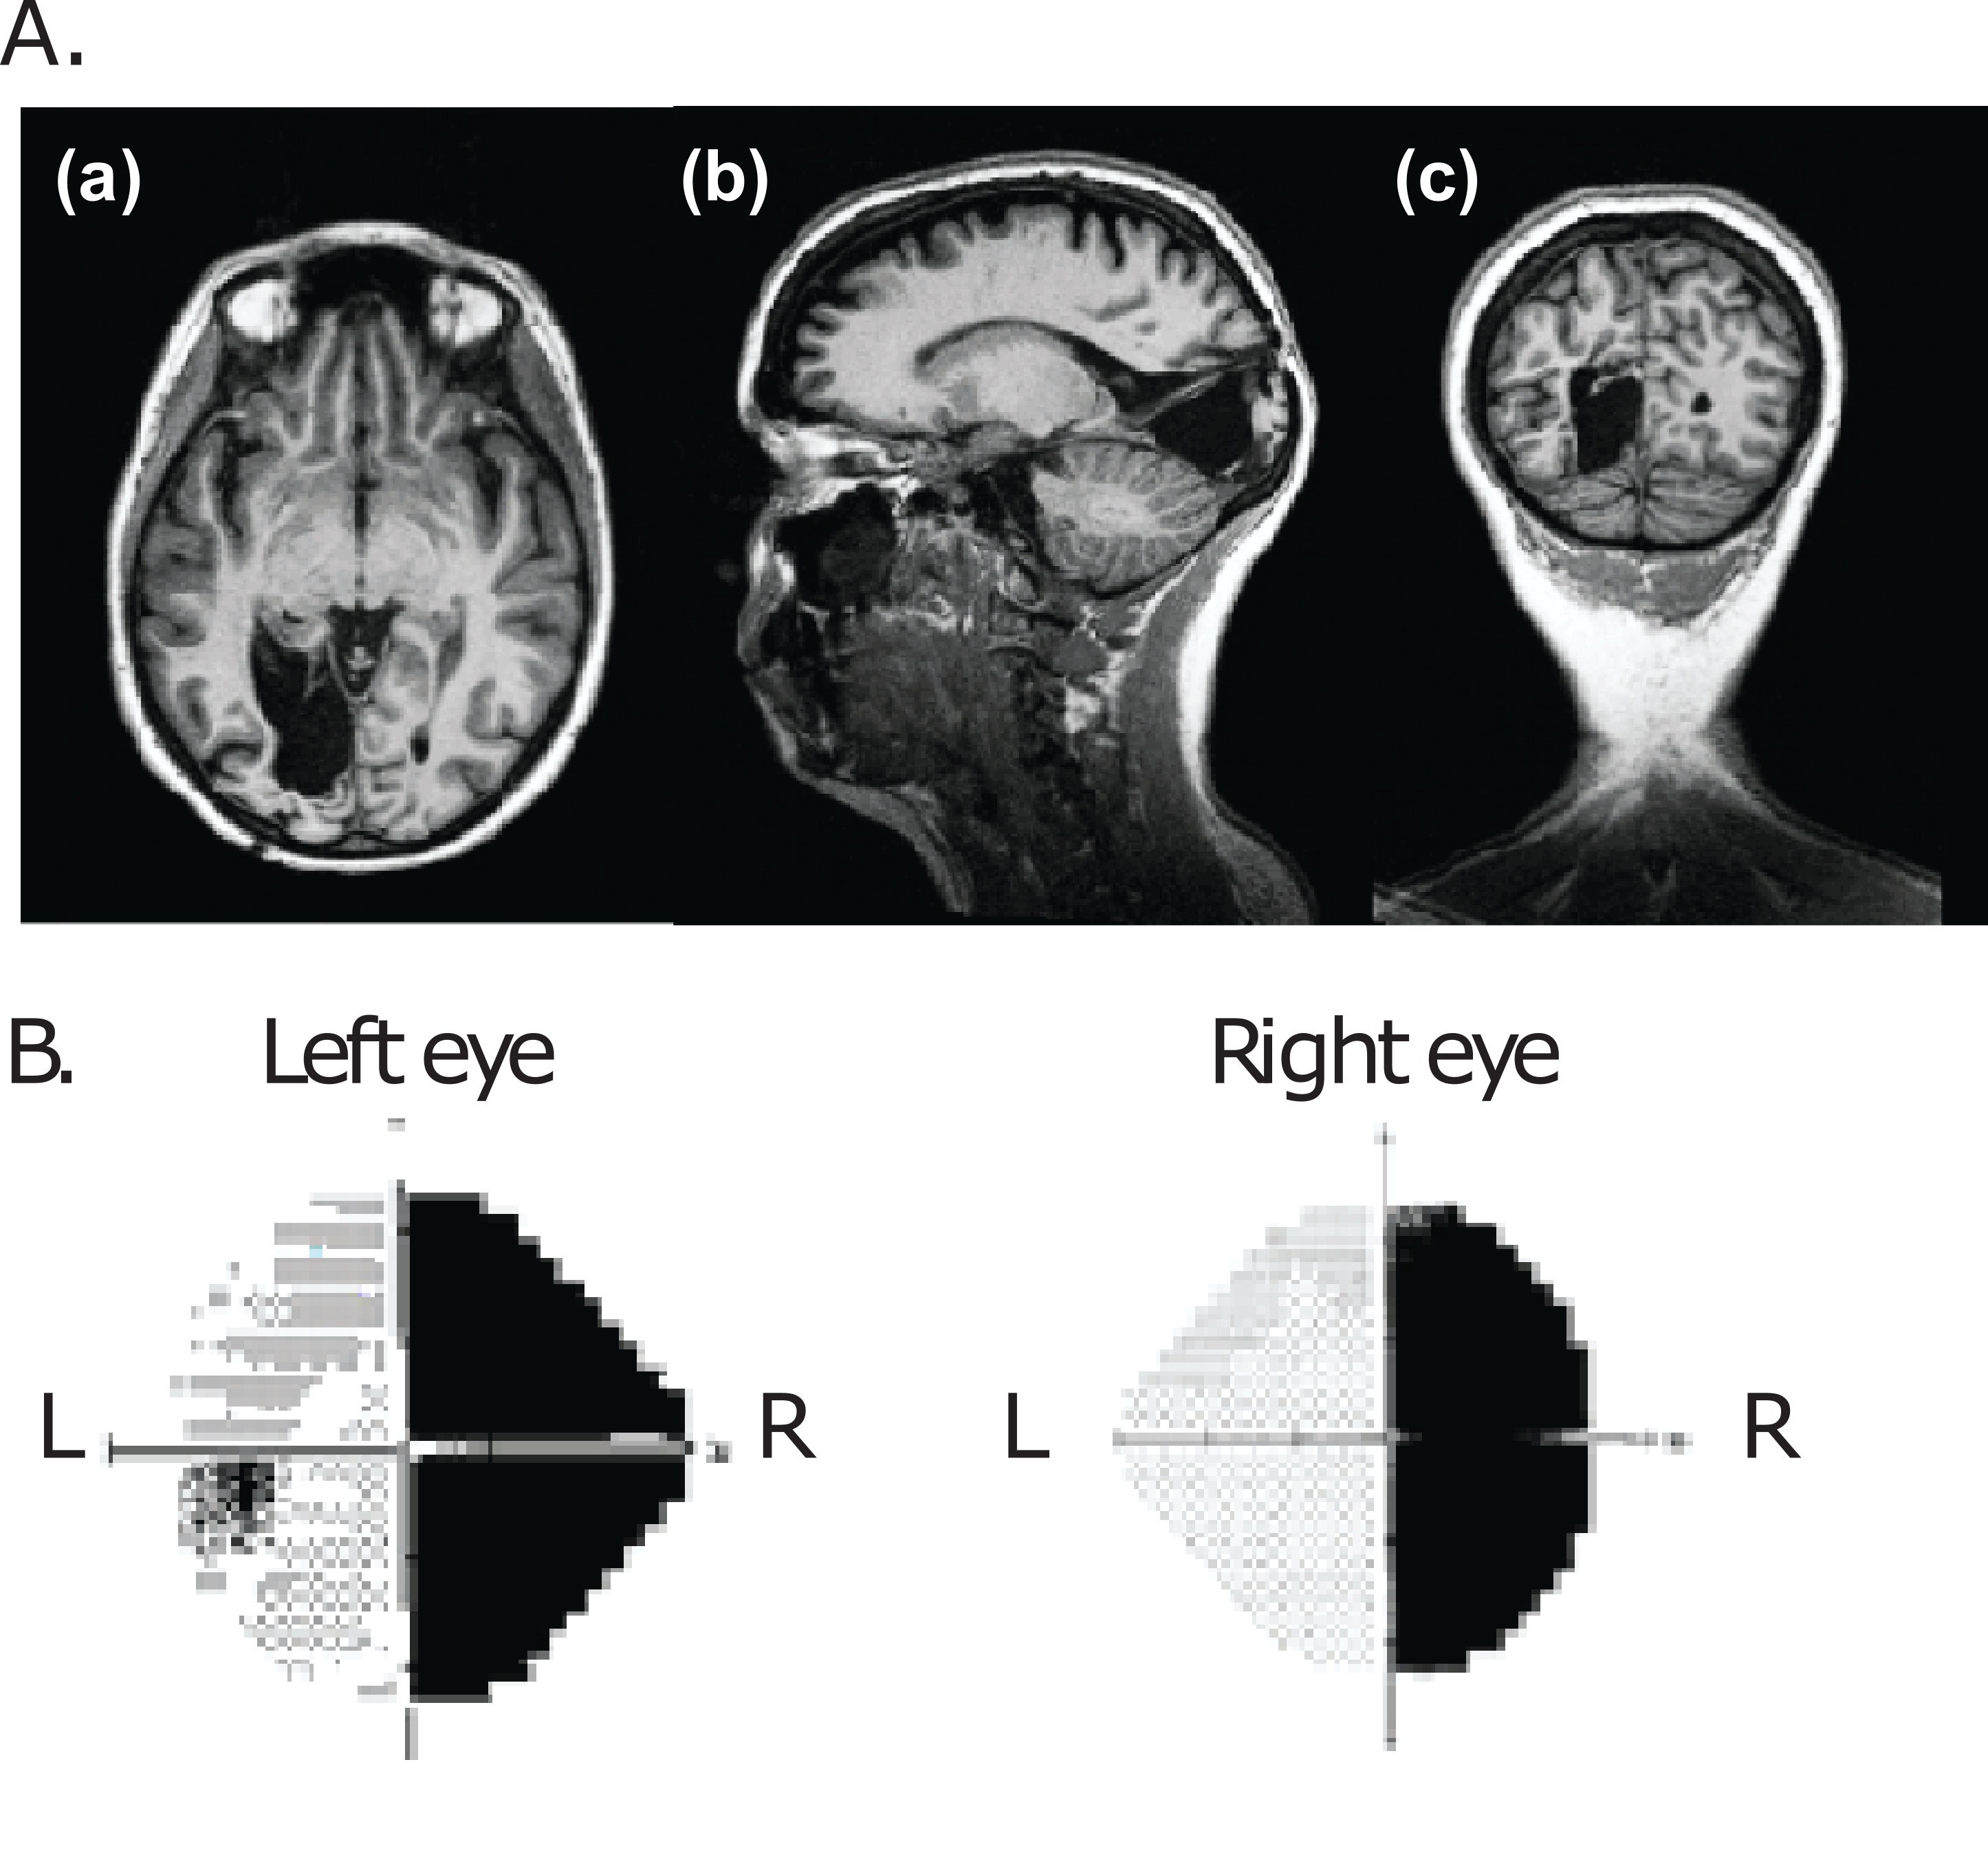

The figure above is an example of an individual with cortical visual impairment to give you an idea of the type of data, where A) shows a T1-weighted anatomical scan with three different slice views showing the primary visual cortex removal in the left hemisphere and the destruction of the primary visual areas (V1) and B) the individual’s visual field showing a symmetric loss across both eyes leading to a complete contralateral visual loss in the right visual field.